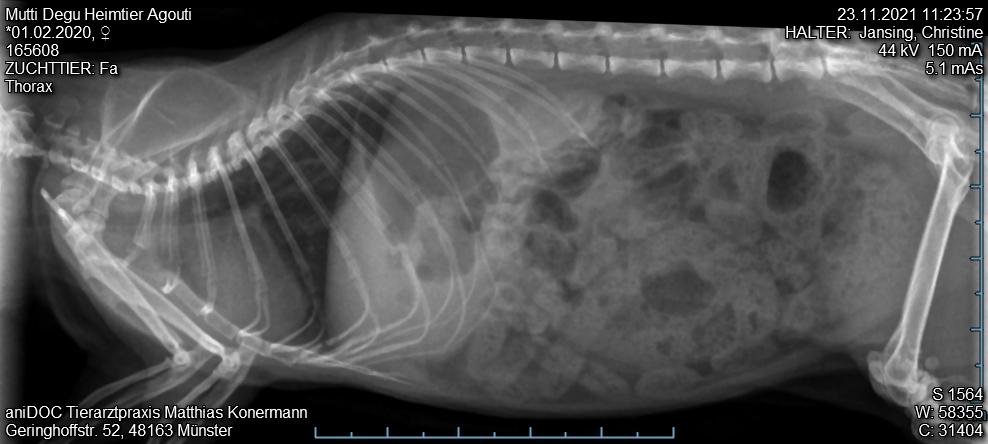

3. Tierarztbesuch am 23.11. Tier merklich mitgenommen, laute Atmung, nun auch beim Abhören der Lunge. Gewichtsverlust etwa 25-30 g. Sehr schwere Flankenatmung. Röntgenbild unter Gasnarkose. Tierarzt sieht nix drauf, Zähne sind aber gut. Verdacht auf Bauchfellentzündung. Neues AB borgal/riketron 24%, 2 Mal täglich 0.5 ml. Dachte, das Tier überlebt die Nacht nicht. Aber Verbesserung seit dem 25.11. Tier frisst wieder, ist bei 189g.